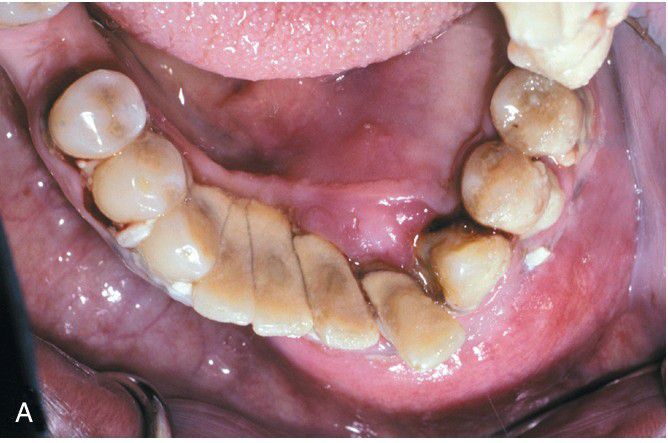

Ameloblastic Carcinoma.

Rapidly growing tumor showing prominent labial expansion of the mandible in the incisor and premolar area. The panoramic radiograph shows irregular destruction of the mandible.